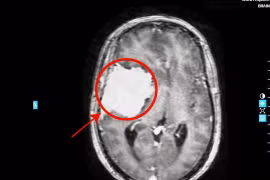

Đau đầu tưởng rối loạn tiền đình, nào ngờ khối u “khổng lồ” ăn mòn xương sọ

Đau đầu tưởng rối loạn tiền đình, người phụ nữ đi khám tại Bệnh viện Đa khoa Tâm Anh phát hiện khối u “khổng lồ” ăn mòn xương sọ, đẩy lệch đường não giữa.